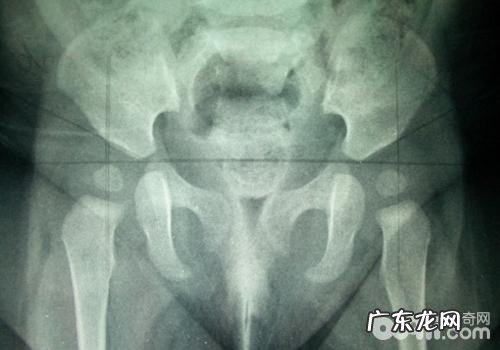

犬髋关发育不全(详细介绍)